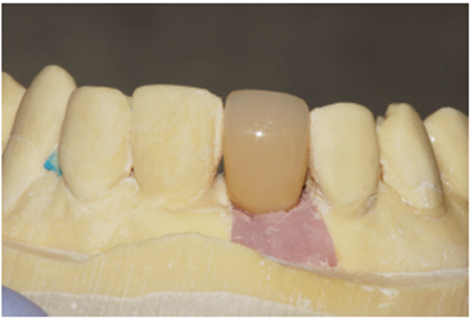

Na consulta seguinte, o cicatrizador foi removido e através do Kit de seleção de componentes, o pilar protético foi selecionado. O pilar de escolha foi o Ideale 3.3 x 4.0 x 1.5 angulado de 30 graus. Neste momento foi realizada uma moldagem com transferente de moldeira fechada (Figuras 25 e 26) para copiar o posicionamento tridimensional do implante e o modelo de trabalho foi obtido.

No laboratório, o técnico de prótese posicionou o pilar Ideale angulado no modelo (Figura 27) e confeccionou um incisivo central parafusado sobre ele, utilizando a coifa de provisório que o sistema oferece (Figura 28). Uma vez obtido o provisório, o cicatrizador voltou a ser removido e o pilar Ideale e o provisório foram instalados em boca (Figuras 30 e 31). O pilar foi torqueado em 20 Ncm e o parafuso da coroa foi torqueado em 10 Ncm. Após 15 dias, o provisório foi removido e observou-se o perfeito perfil de emergência que havia sido obtido (Figura 33). Neste novo momento foi posicionado sobre o pilar um transferente plástico de moldeira fechada do pilar Ideale, sendo que tanto o pilar como o dente 12 foram moldados (Figura 34) para a confecção de copings e posterior a aplicação da cerâmica (Figura 35).